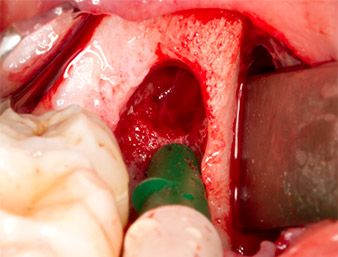

Tras una anestesia local y por conducción, el campo quirúrgico se abrió mediante los tejidos blandos para tener un acceso bucal-retromolar y se dejó expuesto (figura 3).

corte surcular

Imagen 3: El corte surcular comienza en el centro del diente 36, con alargamiento distal en la rama ascendente.

El tejido situado por encima del resto radicular no se había osificado por completo y constaba en su mayor parte de un tejido granulado con alteraciones inflamatorias (figura 4).

tejido granulado

Imagen 4: Dos ganchos de Langenbeck y un raspador según Prichard exponen el campo quirúrgico. Se distingue un tejido granulado de la primera osteotomía que no ha cicatrizado en su totalidad.